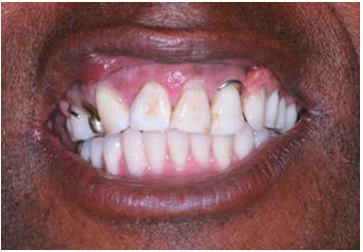

Clinically, the patient presented aesthetic and functional impairment and excessive exposure of the gingival tissue. The patient wore a removable partial denture that presented a mismatch, and only teeth #11, #12, #13, #14, #15 and #21 were present, with grade III mobility. The lower arch presented a fixed full arch hybrid prosthesis previously placed (Figure 1).